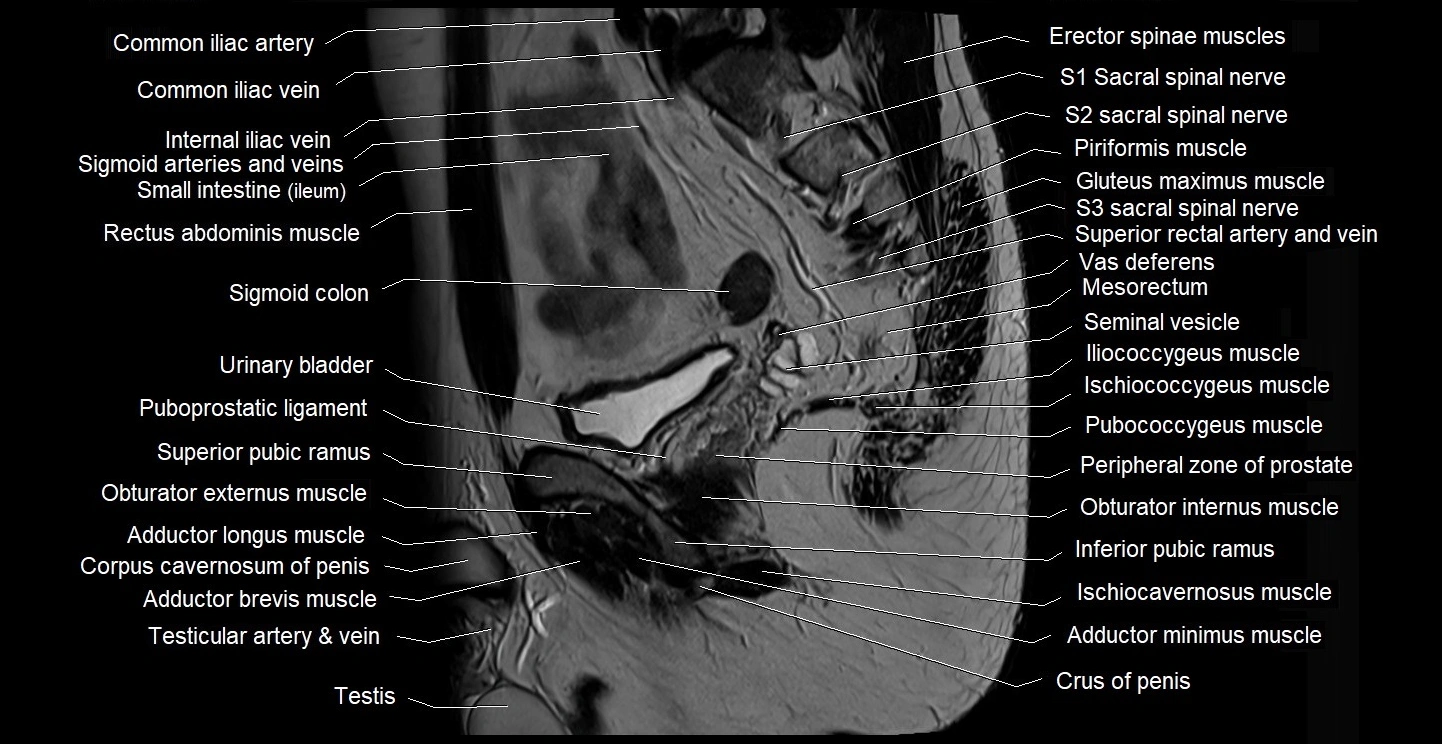

- Central zone of prostate

- Coccyx

- Common iliac vein

- Crus of penis

- Gluteus maximus muscle

- Iliococcygeus muscle

- Ischiococcygeus muscle

- Lumbosacral trunk

- Mesorectum

- Peripheral zone of prostate

- Pubococcygeus muscle

- Puboprostatic ligament

- Seminal vesicle

- Sigmoid colon

- Testis

- Vas deferens